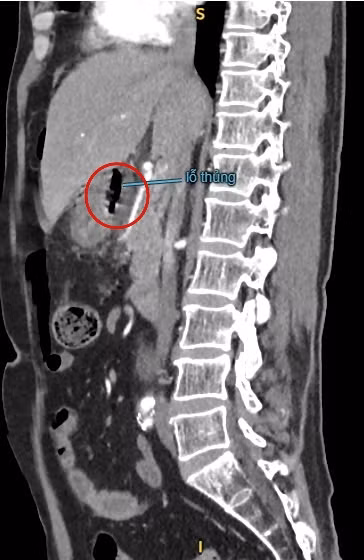

| Hình ảnh thủng tạng rỗng trên CT 160 lát ổ bụng - Ảnh BVCC |

BS.CKII. Nguyễn Vũ An – Trưởng khoa Ngoại Tổng Quát BVĐK Xuyên Á Long An nghi ngờ đây là trường hợp thủng tạng rỗng. Để xác định chẩn đoán, bác sĩ chỉ định chụp CT-scan ổ bụng ghi nhận: viêm phúc mạc do thủng tạng rỗng mặt trước tá tràng – hang vị. Phình động mạch chủ bụng đoạn dưới rốn thận – trên góc chia đôi động mạch chậu. Sỏi thận hai bên.